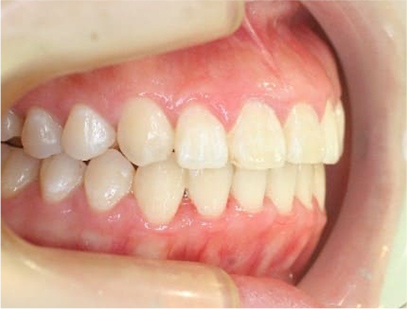

• 右側

• 左側

治療後

• 正面

治療前後の写真を比べると前歯は綺麗に咬み合っていて、上の奥歯が狭かったのが拡大されており下の奥歯と綺麗に咬み合っていることが解ります。治療期間は患者様の協力が大変に良かったために1年半で終了することができ、現在保定治療を行っております。